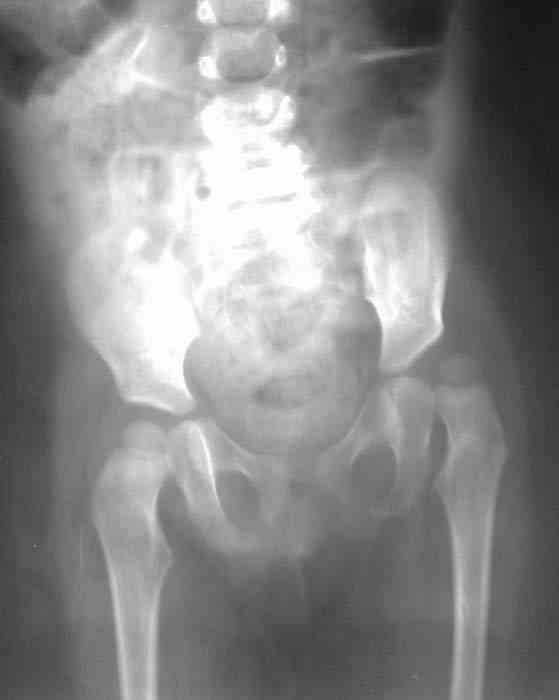

Уважаемые коллеги! Окажите, пожалуйста, консультативную помощь! Девочка, 1 г 9 м ДЗ: врожденная патология головного мозга, врожденная дисплазия, подвывих, приводящая контрактура левого тазобедренного сустава, микроцефалия, миоклонические припадки, грубая задержка психофизического развития, с-м Айкарди?

Жалобы родителей на укорочение левой ноги, невозможность ходить, сидеть. Впервые обратили внимание на укорочение левой нижней конечности 4 месяца назад. Осмотрена по месту жительства в ЦРБ, направлена в ДНИИТО. Ребенок от I беременности, I срочных родов, протекавших с анемией, осложненные преждевременным отхождением вод, вес при рождении 4100. В анамнезе - пупочная грыжа, респираторные заболевания, рахит, тетрапарез, судорожный синдром, сальмонельоз.

Особенности объективного осмотра в настоящее время: Умеренный тетрапарез. Признаки рахита (деформация костей черепа, четки). Дыхание пуэрильное. Тоны сердца ритмичные, шумов нет. Живот мягкий, безболезненный, печень +1,5 см. Склонность к запорам. Местный статус: резкое приведение левого бедра, относительное укорочение левой нижней конечности. Ограничение отведения в тазобедренных суставах, особенно слева. Гипертонус мышц левой нижней конечности. Ограничение сгибания в левом коленном суставе.

Объем движений (левый ТБС): сгибание-разгибание (фиксированное) 65-165; разведение - D 45, S 65. Положение сустава по отношению к линии Розера-Нелатона - D 0,5 см, S 1,5 см. Хронаксиметрия - возбудимость нервных стволов нижних конечностей в норме, двигательная реакция мышц типичная.